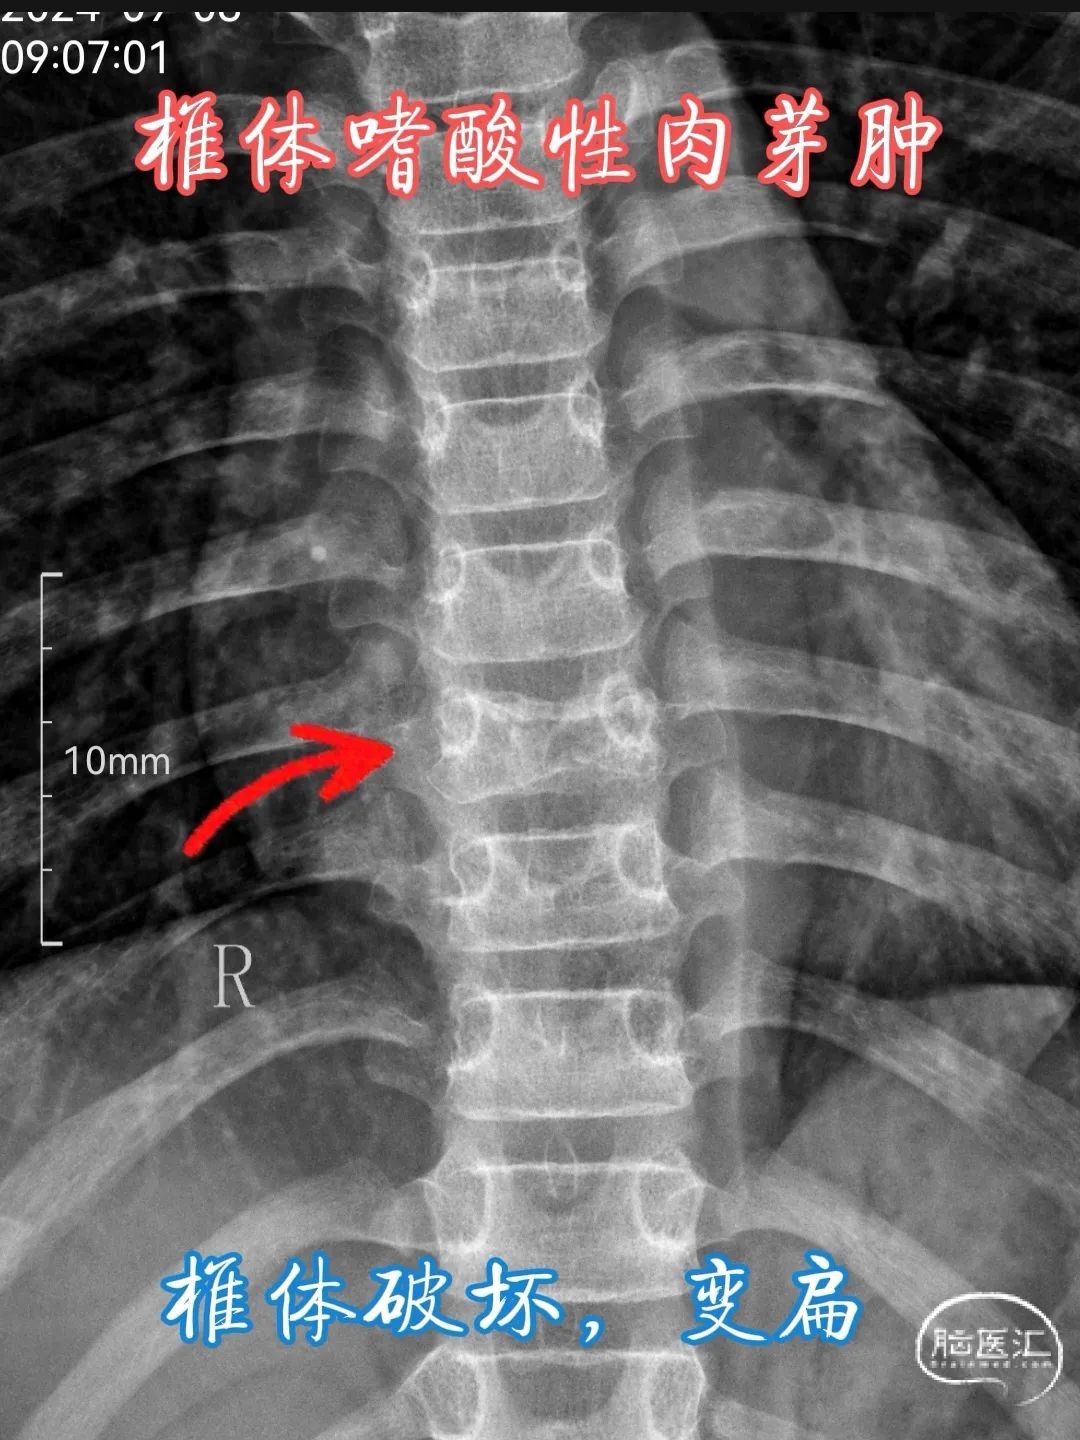

•X 线检查 :椎体嗜酸性肉芽肿在 X 线平片上常表现为椎体的溶骨性破坏,呈单房或多房的透亮影,边缘清晰或模糊,可伴有骨质疏松。典型的 X 线征象包括 “椎体平面”(vertebra plana),即椎体呈扁平状,上下缘平行,椎间隙保持正常,这是由于病变累及整个椎体,导致椎体被压缩变扁,多见于儿童患者。此外,还可能出现椎体楔形变、椎体崩裂等表现,病变周围软组织肿胀也不少见,可呈现为椎旁软组织密度影。